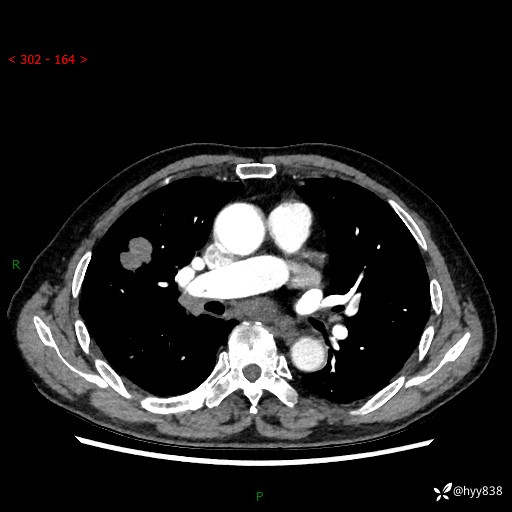

【患者信息】:69岁/男

【主诉】:间断咳嗽伴气促、下肢水肿2周

【现病史及既往史】:患者2周来无明显诱因出现咳嗽,咳少量白痰,不易咳出,伴有气促,呈间断发作,症状与活动费力相关,以夜间为甚,不能平躺入睡,偶有憋醒,无胸闷胸痛、无发热、无头晕、头痛等不适,伴有双下肢中度水肿,就诊于当地县人民医院门诊,完善相关检查提示:左下肢深静脉血栓形成,未予以特殊处理,今患者为求进一步诊治来我院就诊,拟“心衰”收入我科。 起病以来,患者精神、饮食、睡眠可,大小便如常,体力明显下降,体重未见明显减轻。

【检查】:胸部CT增强